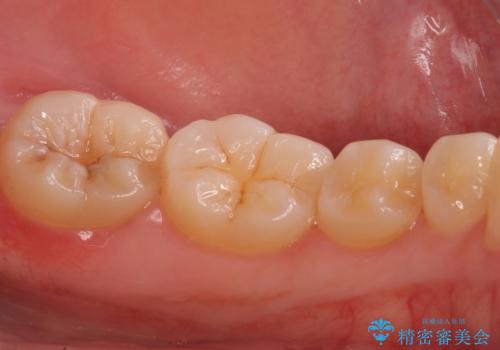

奥歯の虫歯 セラミックインレーでの治療

- 下の奥歯の黒ずみが気になるとのことで来院されました。

検査の結果咬む面に虫歯があることがわかりました。

- 左下7 セラミックインレー 77,000円費用は治療当時の料金となります

削る前は小さな虫歯に見えますが、歯の中で進行しつつある虫歯でした。

虫歯が大きくなると必要な治療が増えてえしまうため早期発見、早期治療を行うことが大事になってきます。